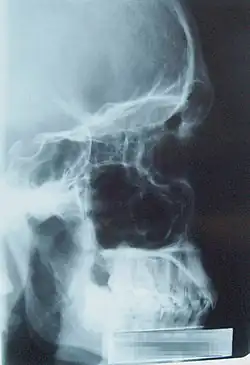

Zatoki przynosowe.

Zatoki przynosowe (łac. sinus paranasales) – przestrzenie pneumatyczne w kościach twarzoczaszki mające połączenie z jamą nosową. Są to wpuklenia błony śluzowej wrośnięte od jamy nosowej w otaczające kości, od których przyjmują swoje nazwy. Zaczynają się one rozwijać u człowieka już w życiu płodowym, ostateczne zaś wymiary osiągają w drugiej dekadzie życia[1]. W rozwoju embrionalnym jako pierwsza wykształca się zatoka szczękowa.